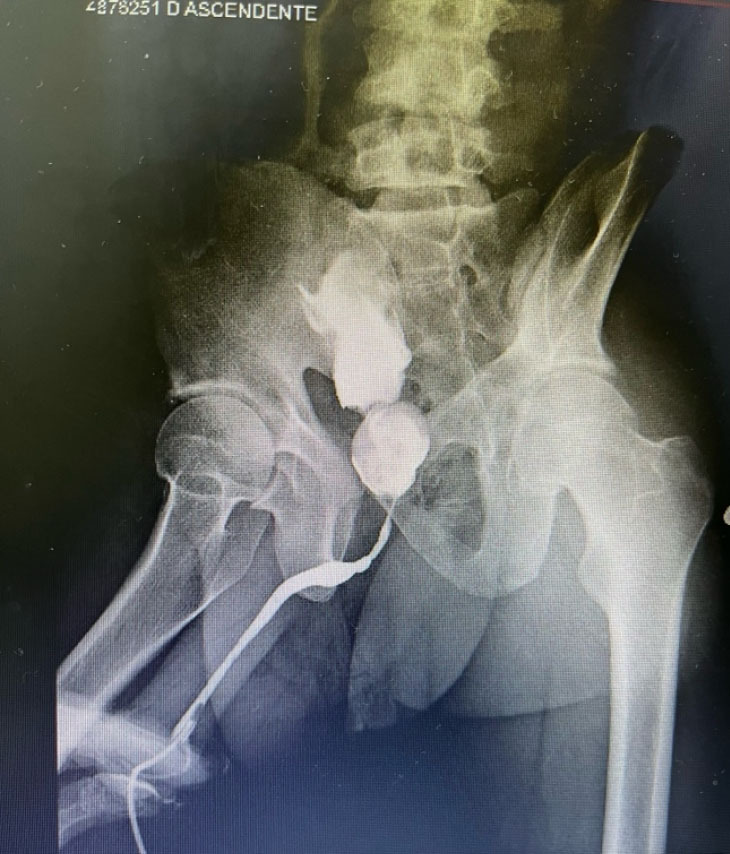

Case description: A 34-year-old male was admitted to the emergency service of a university hospital reporting dysuria and pain in the hypogastrium with a 4-day history. The patient reported that the pain sometimes irradiated to the left flank, accompanied by micturition effort, a weak urinary stream, pollakiuria, and urine output with a crystal appearance. The clinical history revealed urinary difficulty since 10 years of age. The patient was submitted to radiological investigation. Pelvic computed tomography revealed a voluminous calculus with slightly lobulated contours in the intravesical topography in the interior of the prostatic urethra. Urethrocystography revealed a prostatic calculus and the tapered passage of contrast through the prostatic urethra. After the diagnosis, the rectal examination confirmed the presence of a hardened calculous mass in the prostatic topography. Considering the complementary evaluation of the patient, perineal prostatotomy was planned. Prostatotomy was performed longitudinally in the prostatic capsule for the removal of the calculus after its release by dissection.